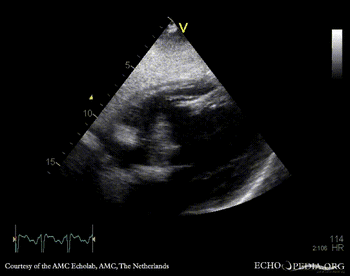

Free wall rupture of left ventricle

E00829.gif E00830.gif

Subcostal view: septal rupture PSAX: septal rupture